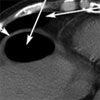

The abdomen was soft and minimally distended, with midepigastric tenderness and tympany. Bowel sounds were hypoactive; there were no peritoneal signs. An upright anteroposterior chest film revealed an elevated right hemidiaphragm with interposition of the transverse colon between the liver and diaphragm (A). A CT scan of the abdomen confirmed that the transverse and ascending colon were interposed anterior and superior to the liver (B). This rare presentation is known as Chilaiditi syndrome and mimics pneumoperitoneum.

Hepatodiaphragmatic interposition of the colon is known as the Chilaiditi sign.1 The prevalence of this anomaly is about 0.025% to 0.28%; it is thought to be more common in men.2 When associated with symptoms, such as pain, nausea, vomiting, abdominal distention, and constipation, the anomaly is called Chilaiditi syndrome.3 The syndrome is thought to be caused by congenital abnormalities of the diaphragm. It may also occur secondary to cirrhosis or chronic lung disease. Review of the literature shows a possible association between Chilaiditi syndrome and volvulus of the transverse colon.4,5 Indeed, in this patient, endoscopic decompression of the colon revealed a partial twisting of the transverse colon, suggestive of a volvulus. His symptoms resolved after the endoscopic procedure.